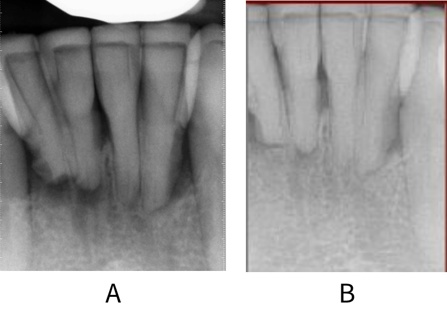

Images taken A: at baseline and B: at 5 years for a patient with Stage IV periodontitis and an extensively restored dentition on a programme of regular maintenance. While the periodontal disease was not completely stable at 5 years, bone infill had occurred around the lower anterior teeth, and inflammation was controlled.